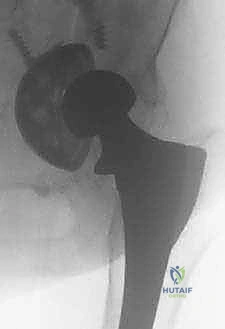

- الأشعة السينية التقليدية (X-rays): صور متعددة الزوايا لتقييم التآكل العظمي، هجرة المكونات، وتحديد تصنيف فقدان العظم (مثل تصنيف Paprosky).

- الأشعة المقطعية (CT Scan): ضرورية للغاية لتقييم مخزون العظم الحُقّي (في الحوض) وتحديد حجم التجاويف العظمية بدقة ثلاثية الأبعاد. تساعد في التخطيط لاستخدام دعامات معدنية أو ترقيع عظمي.

إذا كان المريض يعاني من خلع متكرر لمفصل الورك الصناعي، وكان السبب هو وضع خاطئ للمكونات (Malposition) أثناء الجراحة الأولى (مثلاً الكأس الحُقّي عمودي جدًا أو موجه للخلف)، فلن ينفع أي علاج طبيعي. الحل الوحيد هو إزالة المكون الثابت جراحيًا وإعادة توجيه مكون جديد بالزاوية الميكانيكية الصحيحة.

- المقاربة الخلفية (Posterior Approach): هي الأكثر شيوعًا في جراحات المراجعة. توفر رؤية ممتازة لعظم الفخذ والحُقّ. تتطلب حماية دقيقة للعصب الوركي وإصلاحًا قويًا للكبسولة الخلفية لمنع الخلع.